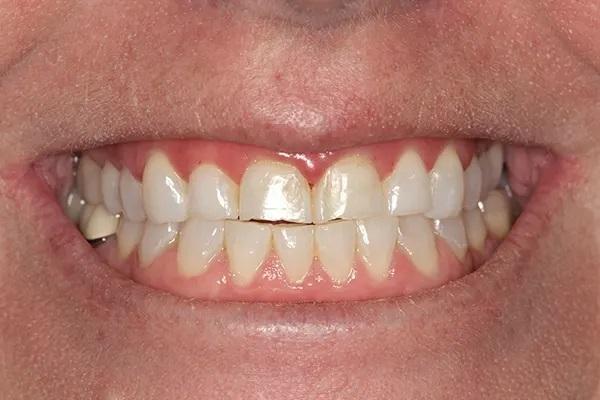

35-летняя пациентка женского пола, наблюдаясь у своего стоматолога с детства выразила заинтересованность в улучшении внешнего вида своих передних зубов, которые в свою очередь, имеют значительные дефекты твёрдых тканей и сколы. Вид улыбки пациентки до лечения "во все зубы" (фото 1); При большом приближении видны сколы во фронтальном отделе зубных рядов (фото 2) Горизонтальный тип стираемости зубов на верхней челюсти (фото 3.). Ее история болезни была отмечена Американским обществом анестезиологов (ASA) II, ввиду ее непереносимости к анестетикам, тем не менее она успешно лечилась с применим препарата Диован. В остальном ее соматическое здоровье никак не отражалось на стоматологическом лечении. В стоматологическом анамнезе у пациенты были выполнены ресторации отдельных зубов и удаление зубов мудрости в подростковом возрасте Представлены прицельные снимки зубов перед восстановительным лечением (фото 4). Также она проходила стоматологическое лечение ранее в детстве. Ее больше всего беспокоил неприглядный вид фронтальных зубов со сколотыми неровными краями на всем протяжении от моляров до первых резцов.

Фото 1

Фото 2